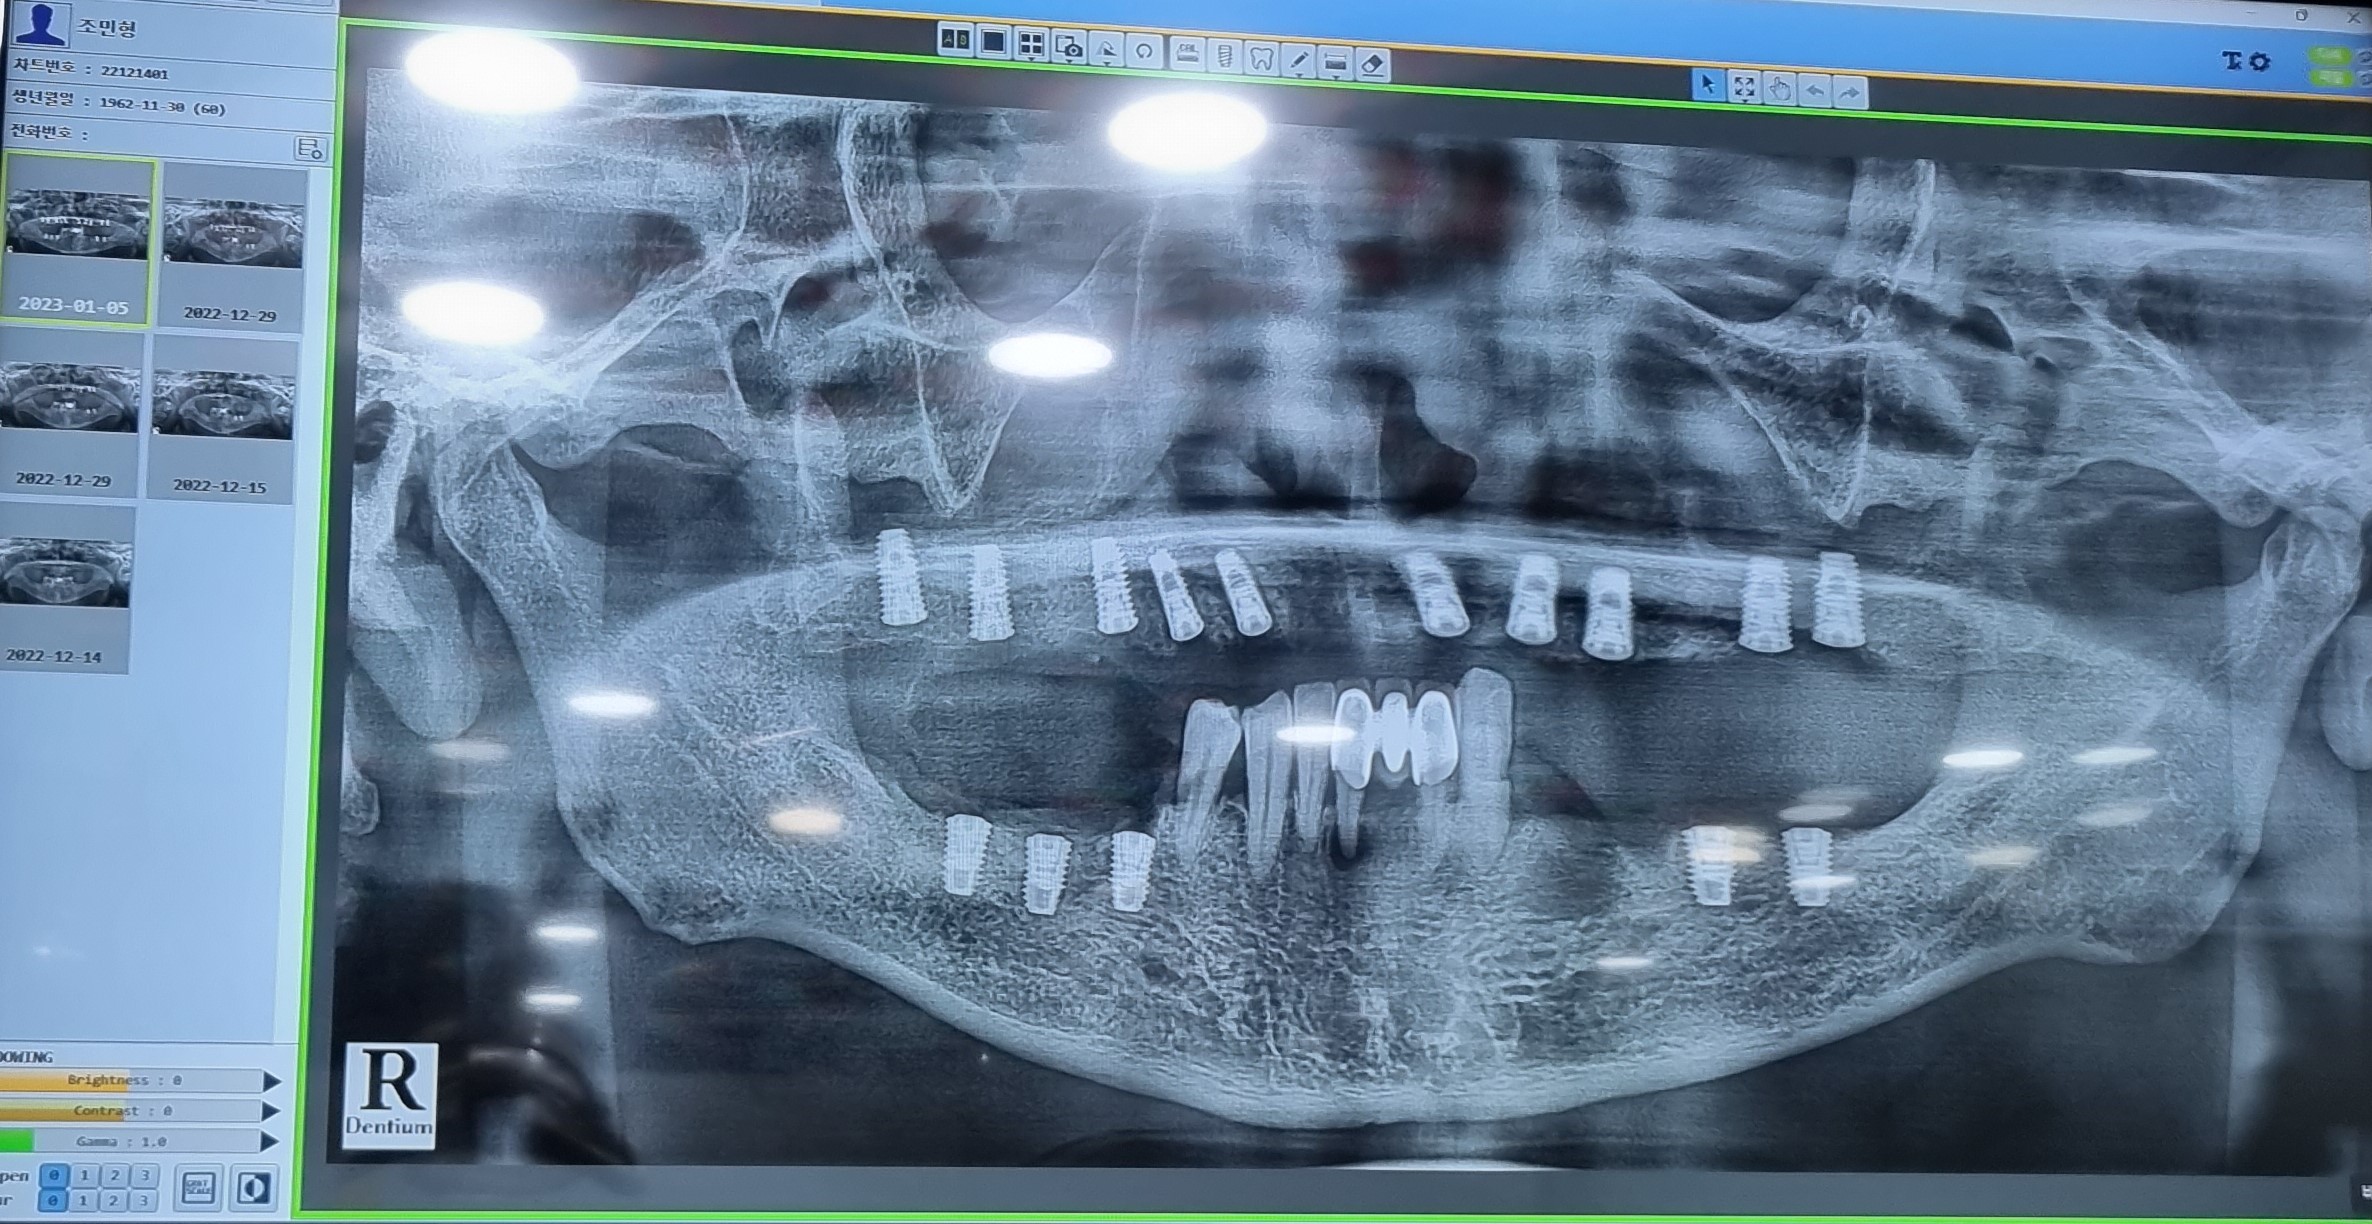

CT 촬영을 통해 구강口腔健康내  상태등을  검사하고  윗턱의  경우  모두  치아齒牙

치주염 齒周炎으로 인하여 결손된 상태라서 자연치아齒牙 2개와

전체  임플란트dental implant와  브릿지bridge를 같이  결합하여

전체  임플란트dental implant의 개수를  낮추는 방향으로  진행 하엿습니다.

임플란트dental implant를  윗니上顎 Over Denture 10   아랫니 下顎 치아齒牙 2 개를

제외하고 대부분의  치아齒牙  치주염 齒周炎 으로  좋지않은  상황이라

발치拔齒 뼈이식과  임플란트 8개를 식립植粒하기로 했습니다.

임플란트dental implant 18개을 식립植粒하는  수술이고.

1 上顎 Over Denture 76 X  32 X   X 23    4 X 67    10

下顎 765       1      XX 3   4 X 67      8

이제  윗니上顎 10X-ray 이미지에서도 모두 1차  수술  치료가  깔끔하게  긑낫습니다.